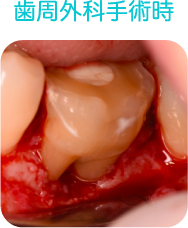

歯周外科治療

歯周基本治療で改善することができなかった深い歯周ポケットの除去

歯周組織の再生